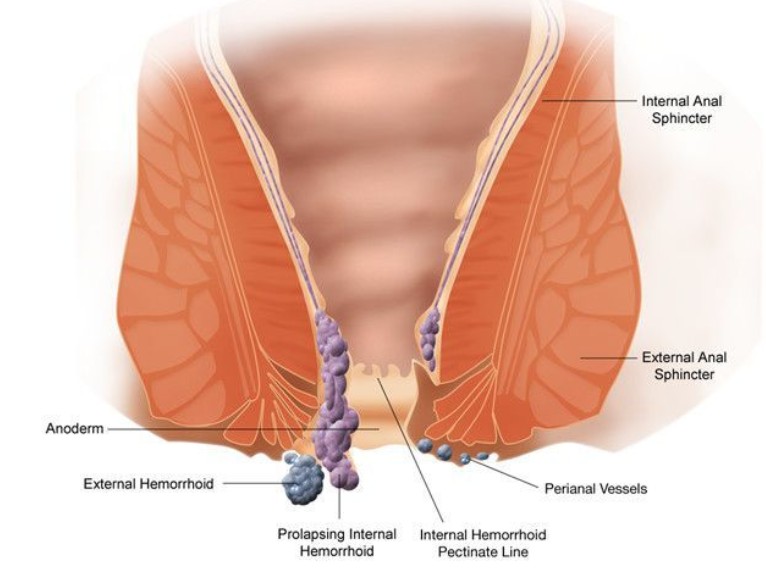

外痔圖片

A:痔瘡是比較常見的肛周疾病,其發生的原因是由於直腸下端,或肛管周圍的黏膜曲張靜脈造成,屬於血管內病變。根據解剖部位的不同,齒狀線以上稱之為內痔,在齒狀線以下稱之為外痔。外痔可以使用稀釋的高錳酸鉀溶液進行坐浴,在坐浴以後同時配合麝香痔瘡膏、痔瘡……

A:痔瘡分為內痔、外痔、混合痔,外痔就是生長在齒狀線以下的一種腫物。這種疾病一般是由炎症以及靜脈迴流等原因所導致的,當病人患上外痔以後一般是可以看得見的,並且這種痔瘡不容易出血。如果病人讓腫塊受到摩擦的話,可能會病人出現疼痛等症狀。臨床上如果……

A:痔瘡是常見的肛周疾病,它是由直腸下段或肛管周圍的黏膜曲張靜脈造成。根據解剖位置的不同,齒狀線以上稱之為內痔,齒狀線以下稱之為外痔。外痔在臨床上大致可分為血栓性外痔、血管源性外痔、炎性外痔,以及結締組織性外痔。血栓性外痔大多是在外痔的血管團……